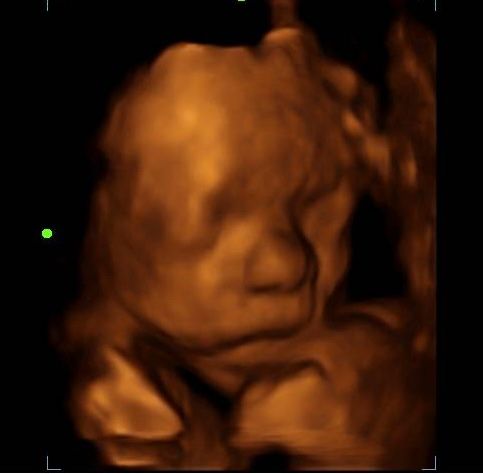

2d, 3d,4d & HD live

Enjoy a private, affordable ultrasound from the comfort of your home, perfect for moms between 7–41 weeks. Share the moment with loved ones by connecting directly to your TV for real-time viewing in 2D, 3D, or 4D. Ideal for baby showers or gender reveal parties!